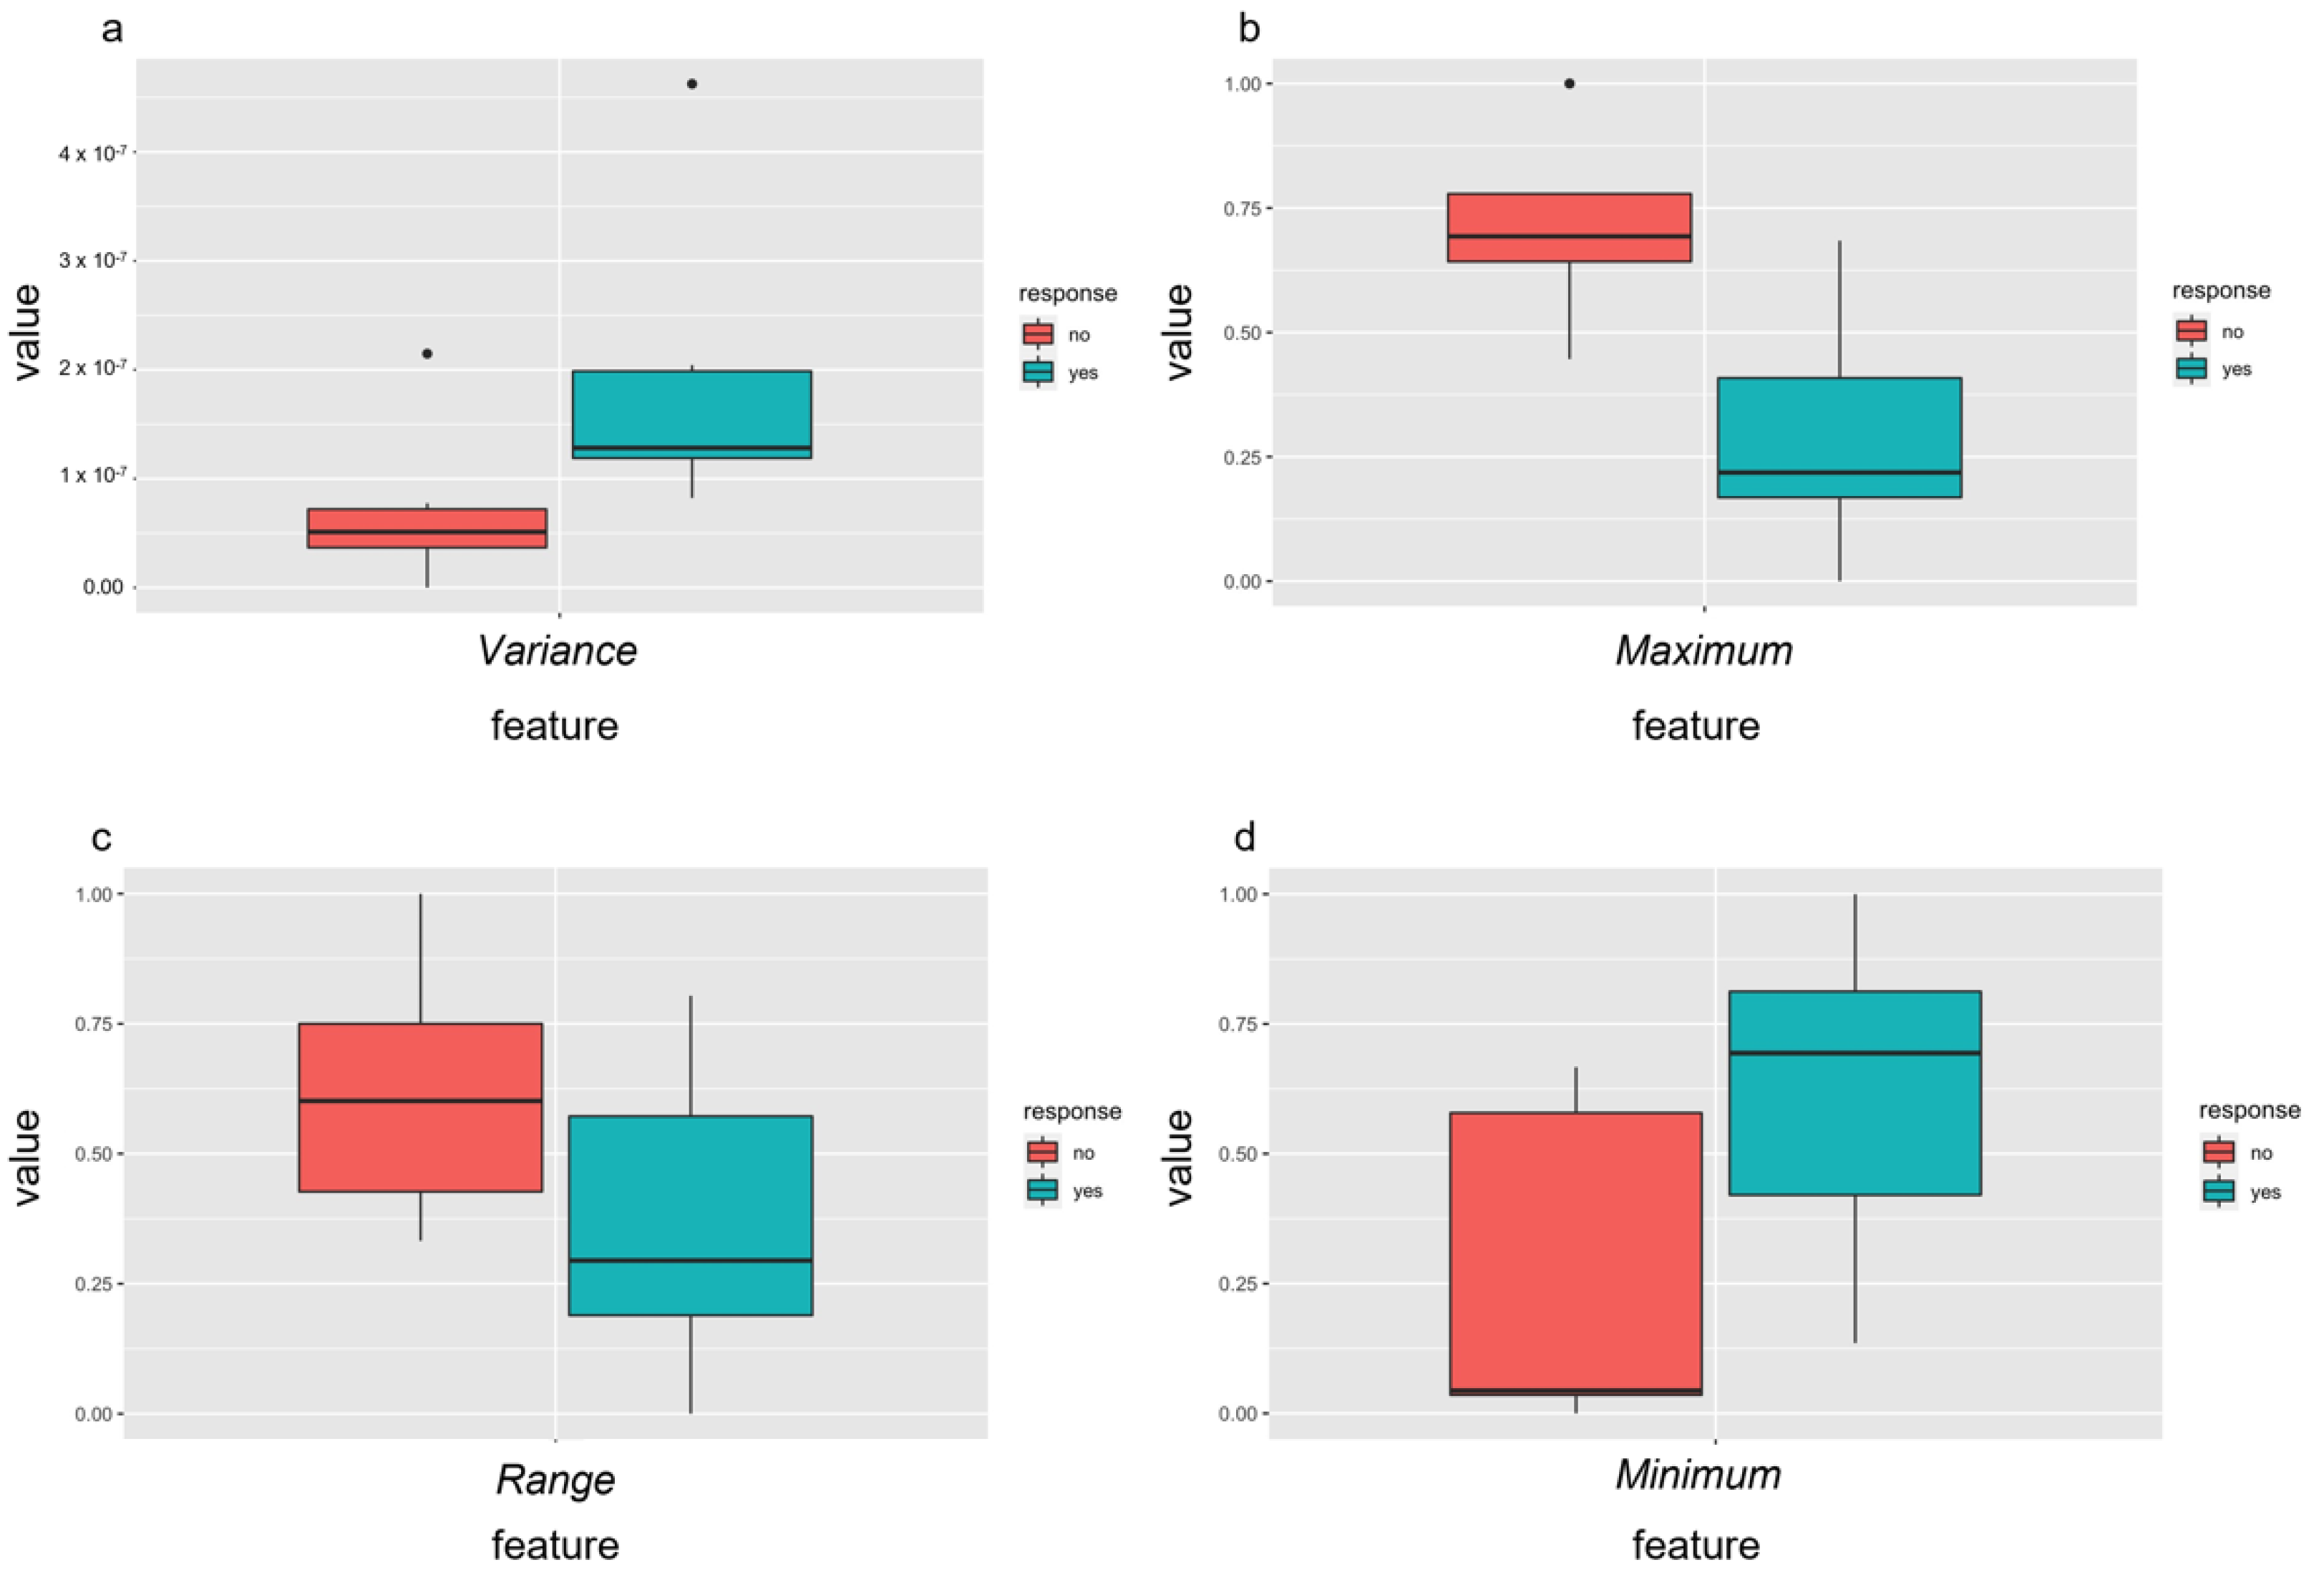

3.5. Outcome Prediction—Radiomics Features before Therapy

3.6. Outcome Prediction—Delta Radiomic Features before and after the First Treatment